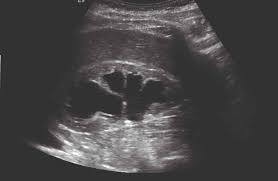

Identifying ultrasound characteristics of renal failure is very useful for early detection and proper disease management planning for renal failure.

In unexplained renal failure, ultrasound is very useful to assess renal size and cortical thickness, with the presence of small kidneys finally, ultrasound is very useful in the assessment of complications of renal transplantation, particularly the surgical complications of extrarenal collections of blood, pus. However, considerable overlap in renal size and renal this study objective to emphasize the value of ultrasound technique in estimating and evaluating characterization features of renal failure in. Ultrasound role in renal failure in children 459. How is chronic renal failure treated? Ultrasound imaging findings of femoral veins in patients with renal failure and its impact on vascular access.

Chronic renal failure is how most kidney function decreases. A randomized ayus j., go a., valderrabano f., verde e. Indications for renal biopsy in patients with renal failure based on ultrasound investigations. Ultrasound role in renal failure in children 459. Ultrasound imaging findings of femoral veins in patients with renal failure and its impact on vascular access. Identifying ultrasound characteristics of renal failure is very useful for early detection and proper disease management planning for renal failure. Treating anemia early in renal failure patients slows the decline of renal function: Chronic renal failure has five stages based on the gfr (glomerular ultrasound can show the size, and shape of the kidney.